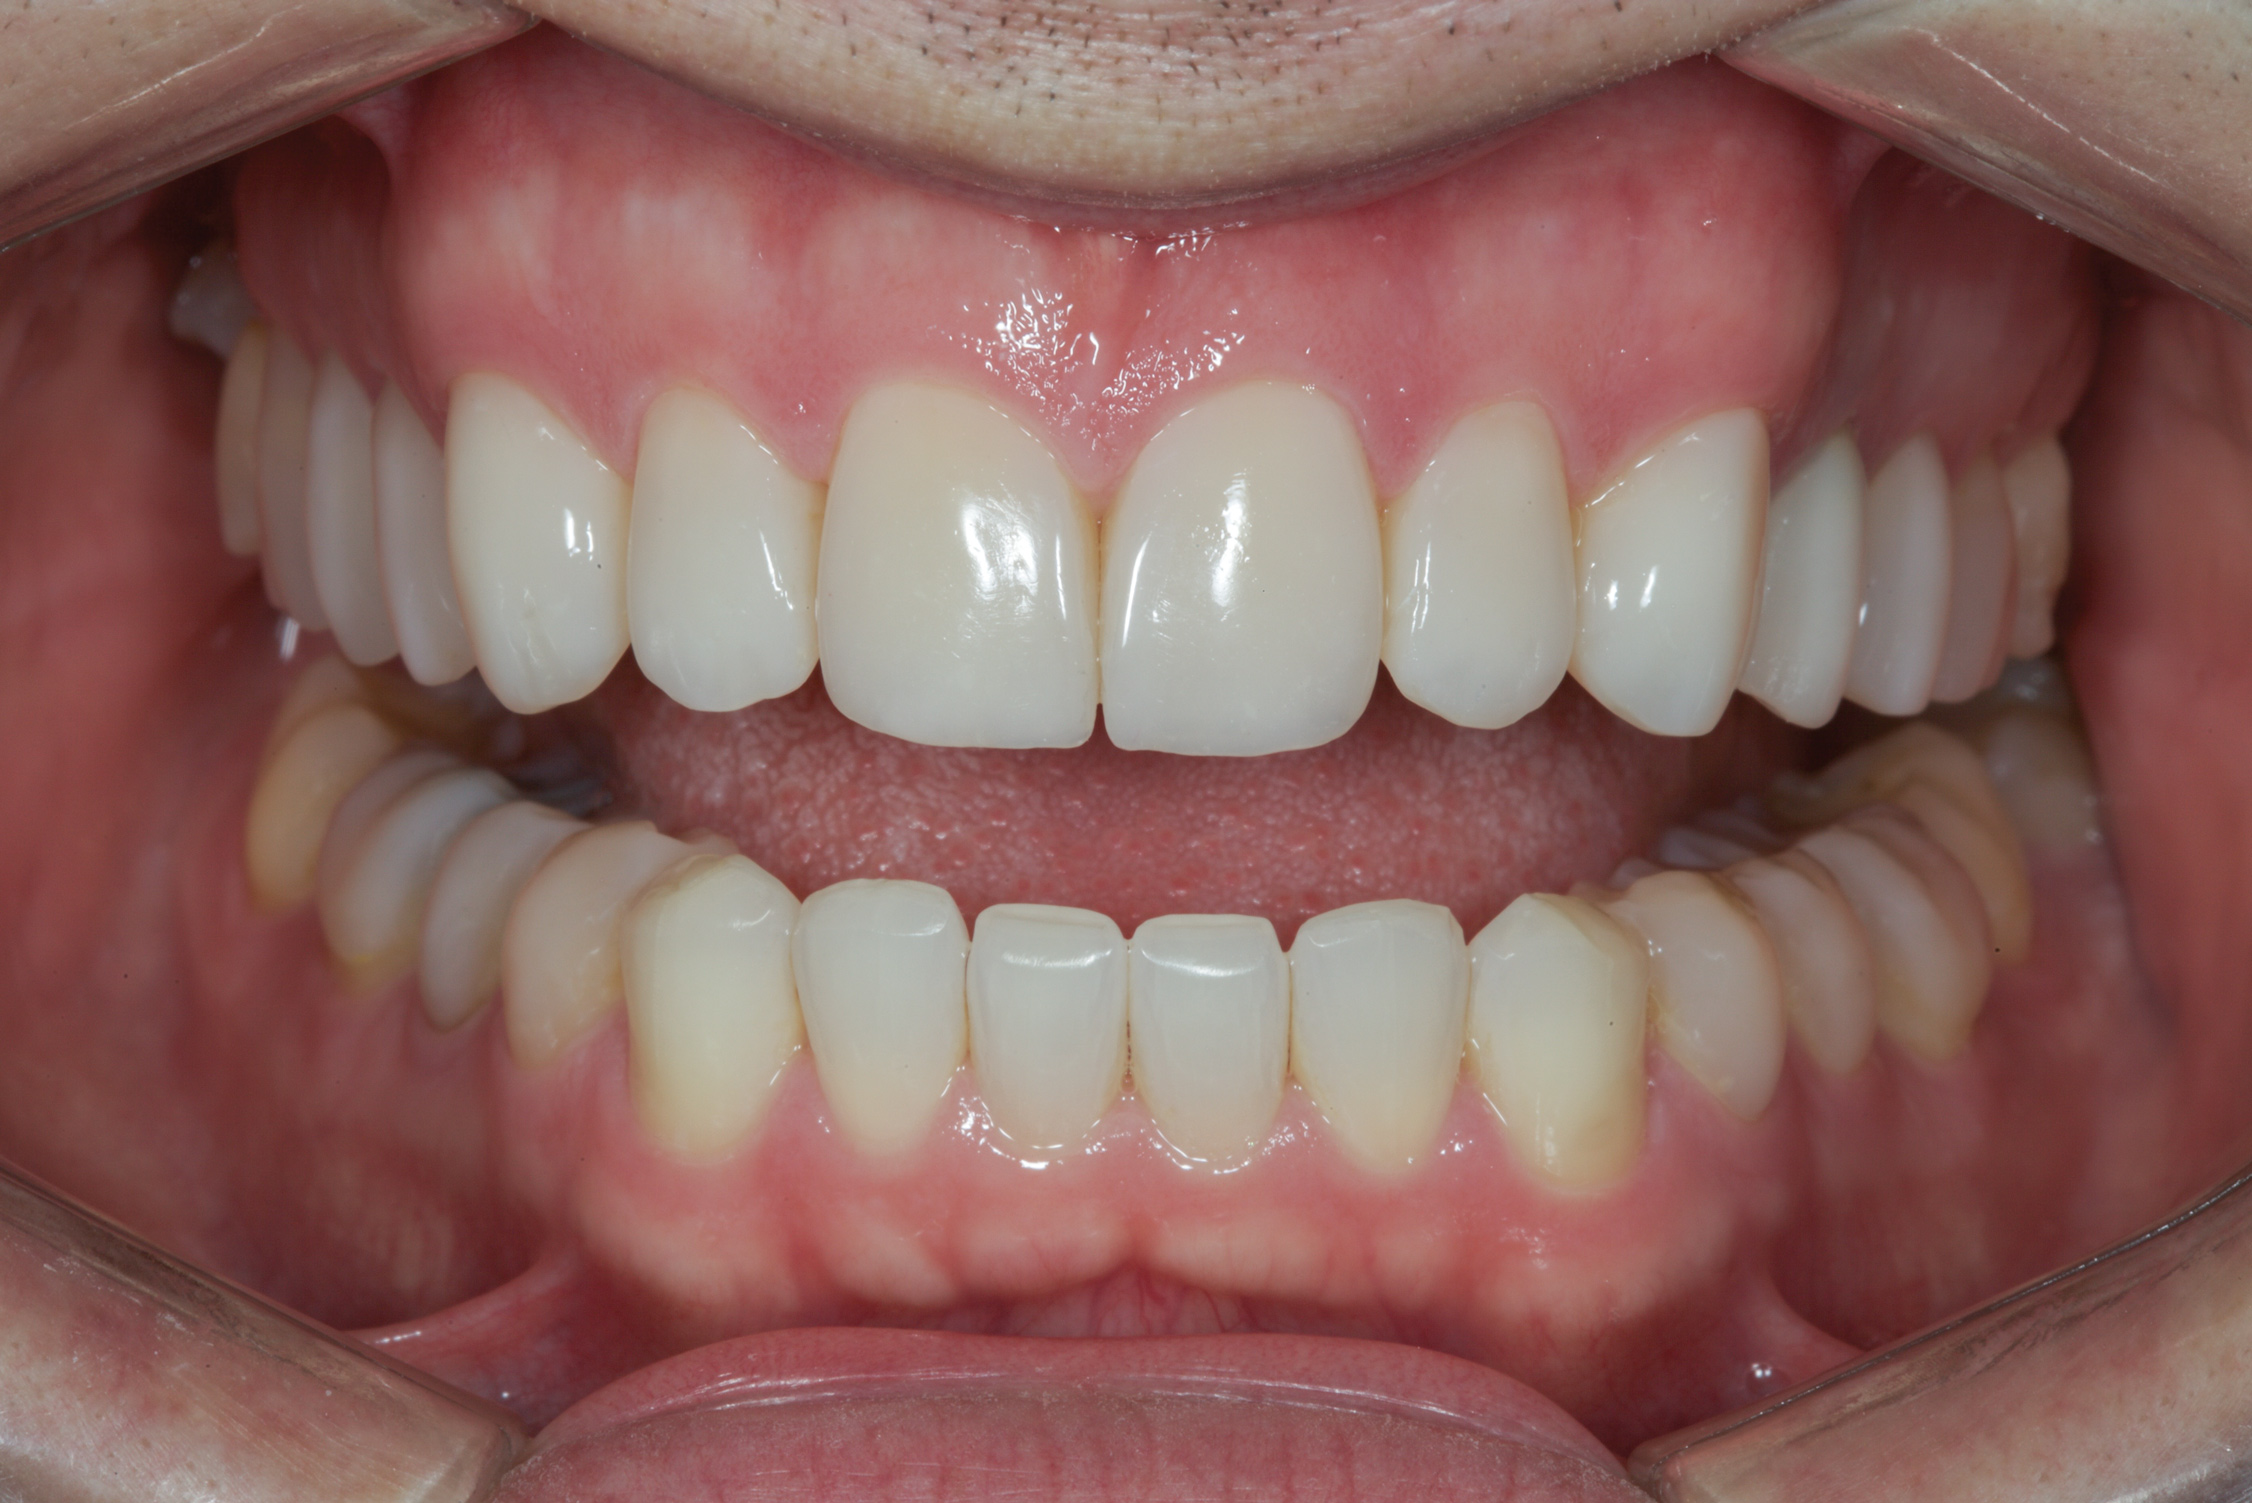

(11.) Postoperative retracted view.

Figure 11

After the composite veneers were finalized, impressions were taken for a monolithic lithium disilicate crown on tooth No. 12. This was placed during a subsequent appointment, and occlusal equilibration was carried out. The patient returned for final photographs a couple of weeks later (Figure 10 through Figure 14).